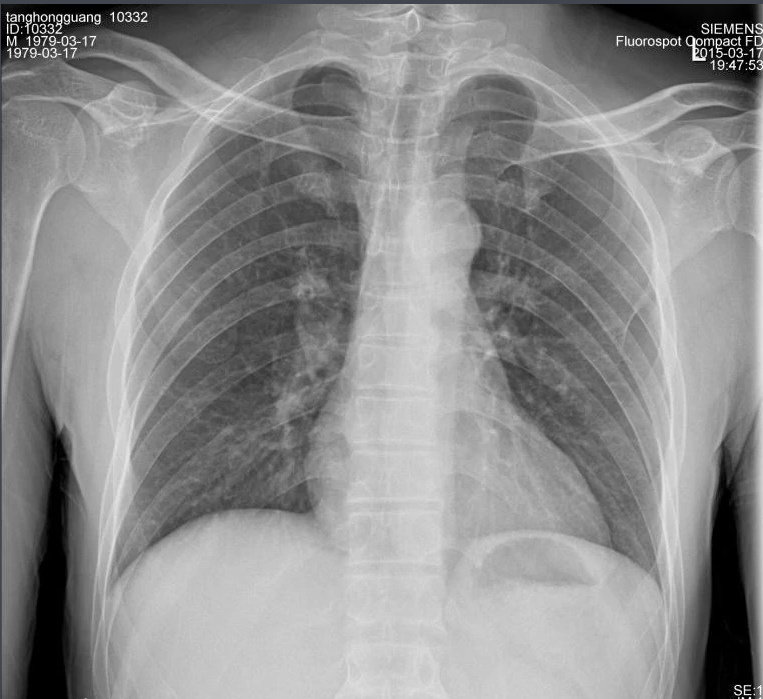

X射线,是一种频率极高,波长极短、能量很大的电磁波。具有穿透性,但人体组织间有密度和厚度的差异,当X射线透过人体不同组织时,被吸收的程度不同,经过显像处理后即可得到不同的影像。下面那ng28.com来聊一聊关于X射线的三大特性分别是哪些。

X射线因其波长短,能量大,照在物质上时,仅一部分被物质所吸收,大部分经由原子间隙而透过,表现出很强的穿透能力。X射线穿透物质的能力与X射线光子的能量有关,X射线的波长越短,光子的能量越大,穿透力越强。X射线的穿透力也与物质密度有关,利用差别吸收这种性质可以把密度不同的物质区分开来 。

X射线同可见光一样能使胶片感光。胶片感光的强弱与X射线量成正比,当X射线通过人体时,因人体各组织的密度不同,对X射线量的吸收不同,胶片上所获得的感光度不同,从而获得X射线的影像  。